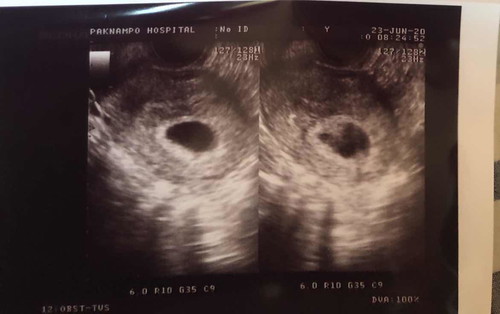

ตั้งครรภ์ได้ 6 w

อยากทราบว่าตั้งครรภ์ได้6wจะพบหัวใจและตัวเด็กไหมคะ ไปซาวด์มาตอน4wพบแต่ถุงการตั้งครรภ์กับถุงไข่แดง แล้วถ้าจับหน้าท้องจะรู้ไหมคะว่ามีหัวใจเต้น

เราไปซาวด์ตอน 5วีค 6 วัน (ซาวด์ภายใน) เจอตัวเด็กและหัวใจค่ะ เค้าให้ฟังเสียงหัวใจด้วย คิดว่าถ้าใช้มือจับหน้าท้องคงไม่รู้ถึงหัวใจที่เต้นนะคะ เพราะว่าน้องคงยังจิ๋วมาก

6วีคก่เจอแบบนี้ค่ะ ผ่านไป รอจนถึง12วีค เราค่อยไปซาวด์ อาให้เห็นน้องชัวร์ๆเลย หัวใจน้องเต้นแรงมาก รออีกหน่อยนะคะ จับท้องดูไม่รู้หรอกค่ะ

ของแม่ 6wน้องกำลังเป็นไข่แดงเล็กๆค่ะ ยังไม่มีหัวใจค่ะ เจอหัวใจน้องเต้นตุ้บๆตอน 8wค่ะ จับหน้าท้องไม่รู้สึกค่ะ

ไปซาวตอน 6w ได้ยินเสียงหัวใจแล้วนะค่ะ แต่ถ้าจับหน้าท้องยังไม่รู้สึกว่าหัวใจน้องเต้นค่ะ

จับหน้าท้องยังไม่รู้ว่าหัวใจเต้นค่ะ บ้านนี้ซาวด์ตอน6-7วีค พบหัวใจและน้องแล้วจ้า🥰

พบหัวใจแล้วจ้าแต่น้องยังไม่เป็นตัวจ้า เป็นเซลล์เล็กๆค่ะแม่ ของบ้านนี้ตอน5w5d